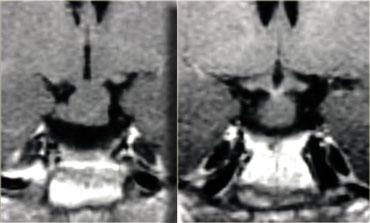

Hình ảnh chuỗi xung T1W và T2W mặt phẳng coronal, cùng với hình ảnh chuỗi xung T1W trước và sau tiêm gadolinium.

Ở bệnh nhân này, tổn thương trong tuyến yên chỉ có thể phát hiện được sau khi tiêm thuốc tương phản từ đường tĩnh mạch.

Chẩn đoán phân biệt: u tuyến yên vi thể hoặc nang khe Rathke.